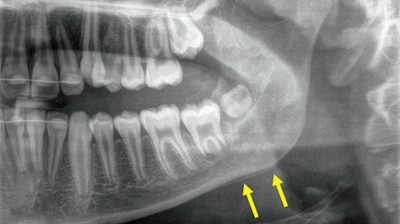

Verlagerte und retinierte Zähne – ein interdisziplinäres Arbeitsfeld

Verlagerte und retinierte Zähne werden in der ersten und noch häufiger in der zweiten Wechselgebissperiode diagnostiziert. Eine frühzeitige Diagnostik kann dazu beitragen, die Eingliederung der Zähne durch eine kombinierte kieferorthopädisch-kieferchirurgische Therapie in die Wege zu leiten. Dieser Fortbildungsbeitrag beschäftigt sich v. a. mit dem fehlenden Durchbruch bleibender Zähne und beschreibt die Zusammenarbeit und das chirurgische Vorgehen bei verlagerten und/oder retinierten Zähnen sowie die Insertion von skelettalen Verankerungssystemen.

Geschwollene Zunge der Patientin/© Munzinger F et al. doi.org/10.1007/s00106-025-01662-9 unter CC-BY 4.0, Illustration eines Zahns im Längsschnitt mit eingebrachter endodontischem Instrument/© Aleksandra Gigowska / Stock.adobe.com, Frau mit schmerzendem Kiefer/© Adiano / stock.adobe.com (Symbolbild mit Fotomodell), Illustration des Ziffernblatts einer Uhr als App-Kachel mit blauem Hintergrund und weißen Zeigern/© Alex White / Fotolia, Osteotomy procedure. Mehrere Hände halten an einem zur OP abgedeckten Gesicht Abhalter in den offenen Mund eines Patienten. Von links ist ein länglicher, mechanisch-robotischer Arm zu sehen, dessen Spitze zum Mund führt./© M. Fu, S. Zhao, X. Zhou, B. Hou, C. Zhang | BMC Oral Health (25)·8, Lungentrainer/© S@photo / stock.adobe.com (Symbolbild mit Fotomodell), Junge Ärztin vor einem Triage-Zelt/© Milos / Stock.adobe.com (Symbolbild mit Fotomodell), Tabletten werden in Hand geschüttet/© O.Farion / Stock.adobe.com (Symbolbild mit Fotomodell), Kranker Junge mit erhöhter Temperatur/© Imgorthand / Getty Images / iStock (Symbolbild mit Fotomodell), Logo DGI e.Academy/© youvivo GmbH / DGI e.V., Okklusale Ansicht Zahn 26: Eingesetztes Individuelles Healing Abutment. Umgebendes Weichgewebe ist mit Nähten fixiert./© Niko Erhard | Die junge Zahnmedizin (16)·2:Centerfold, Zahn 23: Pulpakavum ist vollständig dargestellt. Am Pulpakammerboden lassen sich alle vier Kanaleingänge identifizieren./© M. Hülsmann | Der Freie Zahnarzt (68)·12:58-68, Röntgenbild: Ausschnitt der Oberkieferfrontzahnregion. Zahn 11 und Zahn 21 vorhanden. An Stelle von Zahn 22 ist nur die leere Alveole zu sehen. Weiße Pfeile zeigen auf Zahn 21/© E. Maier, J. Lubauer, K. Galler | Oralprophylaxe & Kinderzahnmedizin (47)·3:161-164, Illustration eines Zahns mit Wurzel im Querschnitt in Knochen. In Zahn und Wurzel ist eine endodontisches Instrument eingebracht./© Maksym Yemelyanov / stock.adobe.com, Illustration eines Zahnbogens mit transparenten Zähnen. In einem Zahn wird eine endodontisches Instrument eingeführt/© Alexandr Mitiuc / stock.adobe.com, Kanüle mit endodontischer Arbeitsspitze, die in einem Messgerät mit Skala zur Bestimmung der Arbeitslänge steckt/© A.D. Nguyen, C. Witting, Ch.R. Gernhardt | Der Freie Zahnarzt (68)·2:56-63, Beispiel einer Mehrschicht- und Mehrfarbentechnik. Aufbau der approximalen Schmelzwände der Zähne 11 und 12 mit individueller Verschalungstechnik und einem Farbverlauf von inzisal nach zervikal/© A. Bolbos | Die junge Zahnmedizin (16)·3:10-19, Zähne einer Seniorin mit Parodontalerkrankung/© Universitätsklinikum Heidelberg, Mädchen hält Zahnbürste mit Zahnpasta/© diamant24 / iStock / Thinkstock, Intraorale Aufnahmen: hochgewölbter Gaumen mit Schleimhautverdickung und kariösen Zähnen/© G. Bilello, A. La Torre, G. Giuliana | Oralprophylaxe & Kinderzahnmedizin (47)·2:83-89, Molaren im UK mit Kavität. Angelegte und einseitig beschliffene Teilmatrize, Abdichtung mit kompaktiertem Teflonband/© C. Mempel, A.-K. Lührs | wissen kompakt (19)·2:75-86, Molaren mit Amalgamfüllung/© icefront / Getty Images / iStock, Orthopantomogramm mit verlagerten Eckzähne und zweiten Molaren im Oberkiefer, Zahnkeime der Sapientes in allen vier Quadranten/© D. Müller-Winter, J. Heider | wissen kompakt (19)·3, Mann erhält eine Spritze im Gesicht/© Alvaro / Stock.adobe.com (Symbolbild mit Fotomodell), Seitliche Ansicht eines Kiefers in Okklusion: Okklusale Abrasion mit komplettem Verlust der Kaufläche sichtbar/© Moataz Bayadse, Mund eines Kindes mit fester Zahnspange und Zahnlücke/© Daria Nipot / Stock.adobe.com (Symbolbild mit Fotomodell), Älterer Mann in hellbraunem Pullover hält sich beide Hände an die Wangen und macht einen besorgten Ausdruck/© Nes / Getty Images / iStock (Symbolbild mit Fotomodell), Antiresorptiva-assoziierte Kiefernekrose/© © O. Ristow, Frontalansicht auf Gebiss in Okklusion: Zähne sind mit gelblich braunem Belag versehen. Zahnfleisch stellenweise gerötet/© J. Kühnisch | Oralprophylaxe & Kinderzahnmedizin (47)·3:184-193, Offener Mund: Wange, Mundboden und Zunge werden von einer bogenförmigen, transparenten Schiene fixiert, die zwischen den Kiefern klemmt./© N. Schulz-Weidner, M. A. Schlenz | Oralprophylaxe & Kinderzahnmedizin (47)·3:198-205, Offener Mund mit herausgestreckter Zunge. in der Mitte der Zunge ist eine große herzförmige und weißliche Verfärbung der Oberfläche zu sehen./© R. Steffen | Oralprophylaxe & Kinderzahnmedizin (47)·2:77-78, Unterkieferfrontzahnbereich: Verbandplatte nach Zahnextraktion im Unterkiefer/© F. Siegberg, P. W. Kämmerer | wissen kompakt (19)·3, Zwei in blaue Arztkittel gekleidete Personen stehen an einem auf dem Behandlungsstuhl liegenden Patienten und führen über eine Lupeninstallationen eine Behandlung im Mund durch/© karrastock / Stock.adobe.com (Symbolbild mit Fotomodellen), Orthopantomogramm eines Unterkiefers mit zwei gelben Pfeilen: Doppelkontur im Bereich des äußeren Kieferwinkels als Ausdruck einer periostalen Knochenapposition, milchglasartige Darstellung des linken aufsteigenden Unterkieferastes/© M. Maurer | Der Freie Zahnarzt (68)·10:64-71, Digitaler Scan und Illustration: Kiefer im seitlichen Profil. Am Kiefergelenk ist eine gelblich dargestellte Endoprothese am Gelenk und Unterkieferknochenansatz zu sehen./© J. Rustemeyer | Die MKG-Chirurgie (17)·3:205-221, Offene Wunde im Oberkiefer und fehlender Frontzahn. Eine weißliche A-PRF-Matrix wird eingebracht./© D. Heimes, E. Naser | wissen kompakt (19)·3, MRT des Beckens: Uterus und Ovarialtumoren/© Hosten AK et al. / all rights reserved Springer Medizin Verlag GmbH, Zahn 11: Zustand nach Sofortimplantation und Bindegewebstransplantation. Zahnlücke mit eingebrachtem Implantat und vernähter Wunde/© A. Rudolph | ZI Zahnärztliche Implantologie (2)·3:144-147, Palatinale Ansicht eines Oberkiefers mit metallisch überkronter Restbezahnung und Zahnlücken/© J.M. Stein | Die MKG-Chirurgie (18)·2:116-123, Klinische Abbildung: mehrere freigelegte enossale Implantate im Kieferkamm mit horizontalem Knochenabbau/© S. Becher | Die MKG-Chirurgie (18)·2:133-140, DGI-Podcast. Blauer Hintergrund in mehreren Schattierungen. im Vordergrund Textzug: Dr. Christian Hammächer. Parodontitis-Patienten implantieren - Wann und wie sicher umsetzen?/© DGI-Deutsche Gesellschaft für Implantologie GmbH, Gute Frage - Gute Antwort/© [M] MclittleStock / Stock.adobe.com (modifiziert durch Springer Verlag), DGI-Podcast. Blauer Hintergrund in mehreren Schattierungen. im Vordergrund Textzug: Prof. Knut A. Grötz. Rechtssicher aufklären - Erstgespräch bis Dokumentation/© DGI-Deutsche Gesellschaft für Implantologie GmbH, Roboterhand hält zahnmedizinisches Röntgenbild vor dem Hintergrund einer Behandlungsleuchte/© phonlamaiphoto / stock.adobe.com, Ausschnitt einer Krankenversichertenkarte/© [M] YK / stock.adobe.com, modifiziert vom Springer Verlag, Gesicht mit zugekniffenen Augen und gerunzelter Stirn/© L Ismail / peopleimages.com / stock.adobe.com (Symbolbild mit Fotomodell), Korbinian Benz/© K. Benz | Die junge Zahnmedizin (16)·2:48-52, Digitale Modelldarstellung eines zirkulären Provisoriums (Zahnreihe im Oberkiefer weiß, Zahnreihe im Unterkiefer und restliches Mockup gelb)/© S.M. Blender, H. Rudolph | wissen kompakt (19)·2:68-74, Während die Quadrantenstütze des Vertikalextraktorsystems auf den Zähnen 12, 13, 22 und 23 aufliegt, wird Zahn 21 mit einer Seilwinde nach dem Flaschenzugprinzip herausgezogen/© S. Kistler | ZI Zahnärztliche Implantologie (1)·4:228-237, Aufsicht auf Kaufläche eines Molar mit Molaren-Incisiven-Hypomineralisation isoliert durch hellblauen Kofferdamm/© A. I. Guzman de Hoyos | Oralprophylaxe & Kinderzahnmedizin (46)·4:290-291, Pflegebett mit Rausfallschutz und Fernbedienung/© Alterfalter - Fotolia, Zwei zahnmedizinische Vollprothesen die aufeinanderliegen/© Eshma / Getty Images / iStock, Ulzerative Form des oralen Lichen planus/© Abdusalamov K. et al. doi.org/10.1007/s00105-025-05540-x unter CC-BY 4.0, Blutige Mukositis Tag 9 nach stationärer Aufnahme/© Kolbe H et al. / all rights reserved Springer Medizin Verlag GmbH, Springer Medizin Podcast - Trigeminusneuralgie/© (M) pain au chocolat / stock.adobe.com (Symbolbild mit Fotomodell), Gaumen im offenen Mund: Symmetrische, leicht erhabene, unscharf begrenzte Erythroplakie am Hartgaumen beidseits/© M. Niu, J. Shakhtour, K.D. Wolff | Die MKG-Chirurgie (18)·2:148-151, Orthopantomogramm: auf dem Bild sind mehrere Implantate im Ober und Unterkiefer sowie nicht emmergierte Zähne zu sehen/© G. Trento, T. Joanning, H. Parize, L. Daume, J. Kleinheinz | wissen kompakt (19)·1:16-24, Arzt führt bei Patienten auf zahnmedizinischem Behandlungsstuhl eine Untersuchung mit einem Ultraschallgerät vor. Der Arzt hält das Handstück an den Kiefer des Patienten./© D.G.E. Thiem, S. Vinayahalingam | Die MKG-Chirurgie (18)·1:37-43, Zervikale Resorption an 14/© S. Neumeyer | wissen kompakt (18)·3:92-98, MRT-Bildgebung mit Kontrastmittel: Schädel mit raumforderndem Prozess auf Höhe des linken Kiefergelenks/© P. Gebhart, G. Levidou, J. Stix, A.W. Eckert | Die MKG-Chirurgie (17)·3:194-199, Isolierte Fraktur der Stirnhöhlenvorderwand/© Albrecht T. et al. / all rights reserved Springer Medizin Verlag GmbH, DGI-Podcast. Blauer Hintergrund in mehreren Schattierungen. im Vordergrund Textzug: Prof. Dr. Dr. Bilal Al-Nawas. Zwischen OP und Privatleben - Die Strategien von Prof. Al-Nawas/© DGI-Deutsche Gesellschaft für Implantologie GmbH, Penicillinallergie an der Hand/© Halling, F., Kronenberger, B. | Die MKG-Chirurgie (18)·3:218-225, Logo